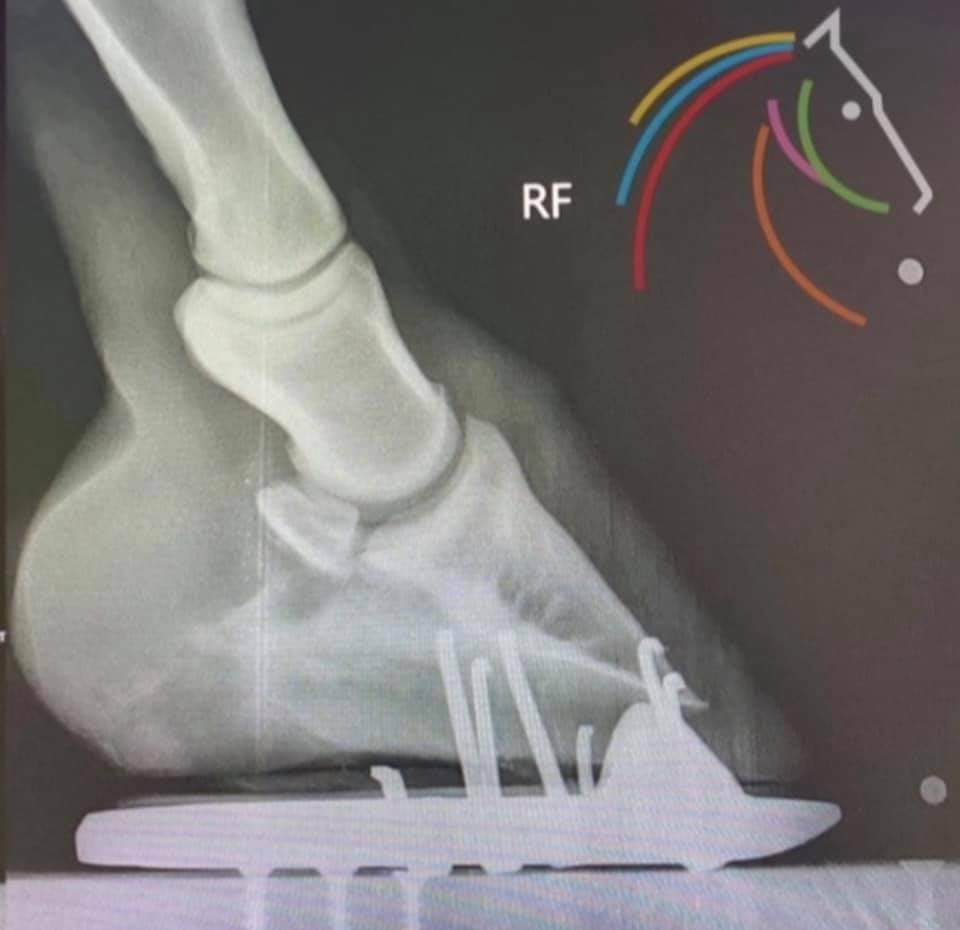

Resultat efter stimulering av stötdämpningsstrukturen;

BILD 1. Hoven var från början skodd med en vanlig järnsko, öppen baktill, alltså utan något stöd för det stötdämpande området bak i hoven.

BILD 2. Resultat efter 4 specialskoningar med stöd för stötdämpningens strukturer.

Hämtat från The Lowly Farrier